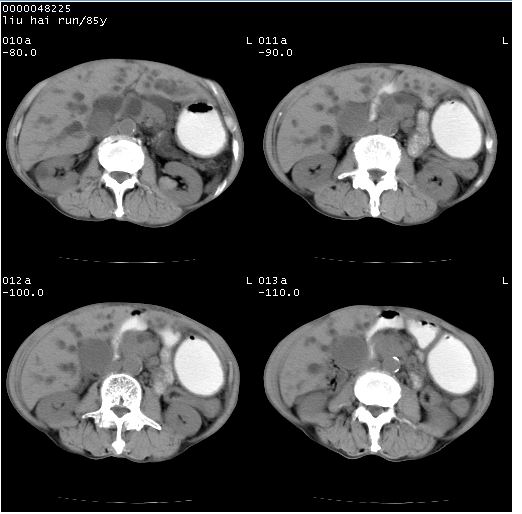

标题: CT13403:M,85Y。胆系低位梗阻。胰头占位?

彩超示胰头实质欠均匀,胰管扩张。

影像表现:壶腹部扩张胆管呈截断样改变,肝内外胆管重度扩张,胆囊增大,胰管亦明显扩张,呈不规则患珠样,胰体尾部略有萎缩,增强扫描后壶腹部低密度影轻度强化,与钩突分界不清。

ct诊断:胆管癌。鉴别诊断:胰腺癌,胰腺癌为少血供肿瘤,增强后强化不明显,静脉期及延时后与正常胰腺分界清晰。

双肾多发囊肿

1)胆系低位梗阻(肝内外胆管扩张、胰管扩张、胆囊增大);考虑为:胰头癌可能性大,不排除胆总管下端癌。2)双肾多发囊肿。